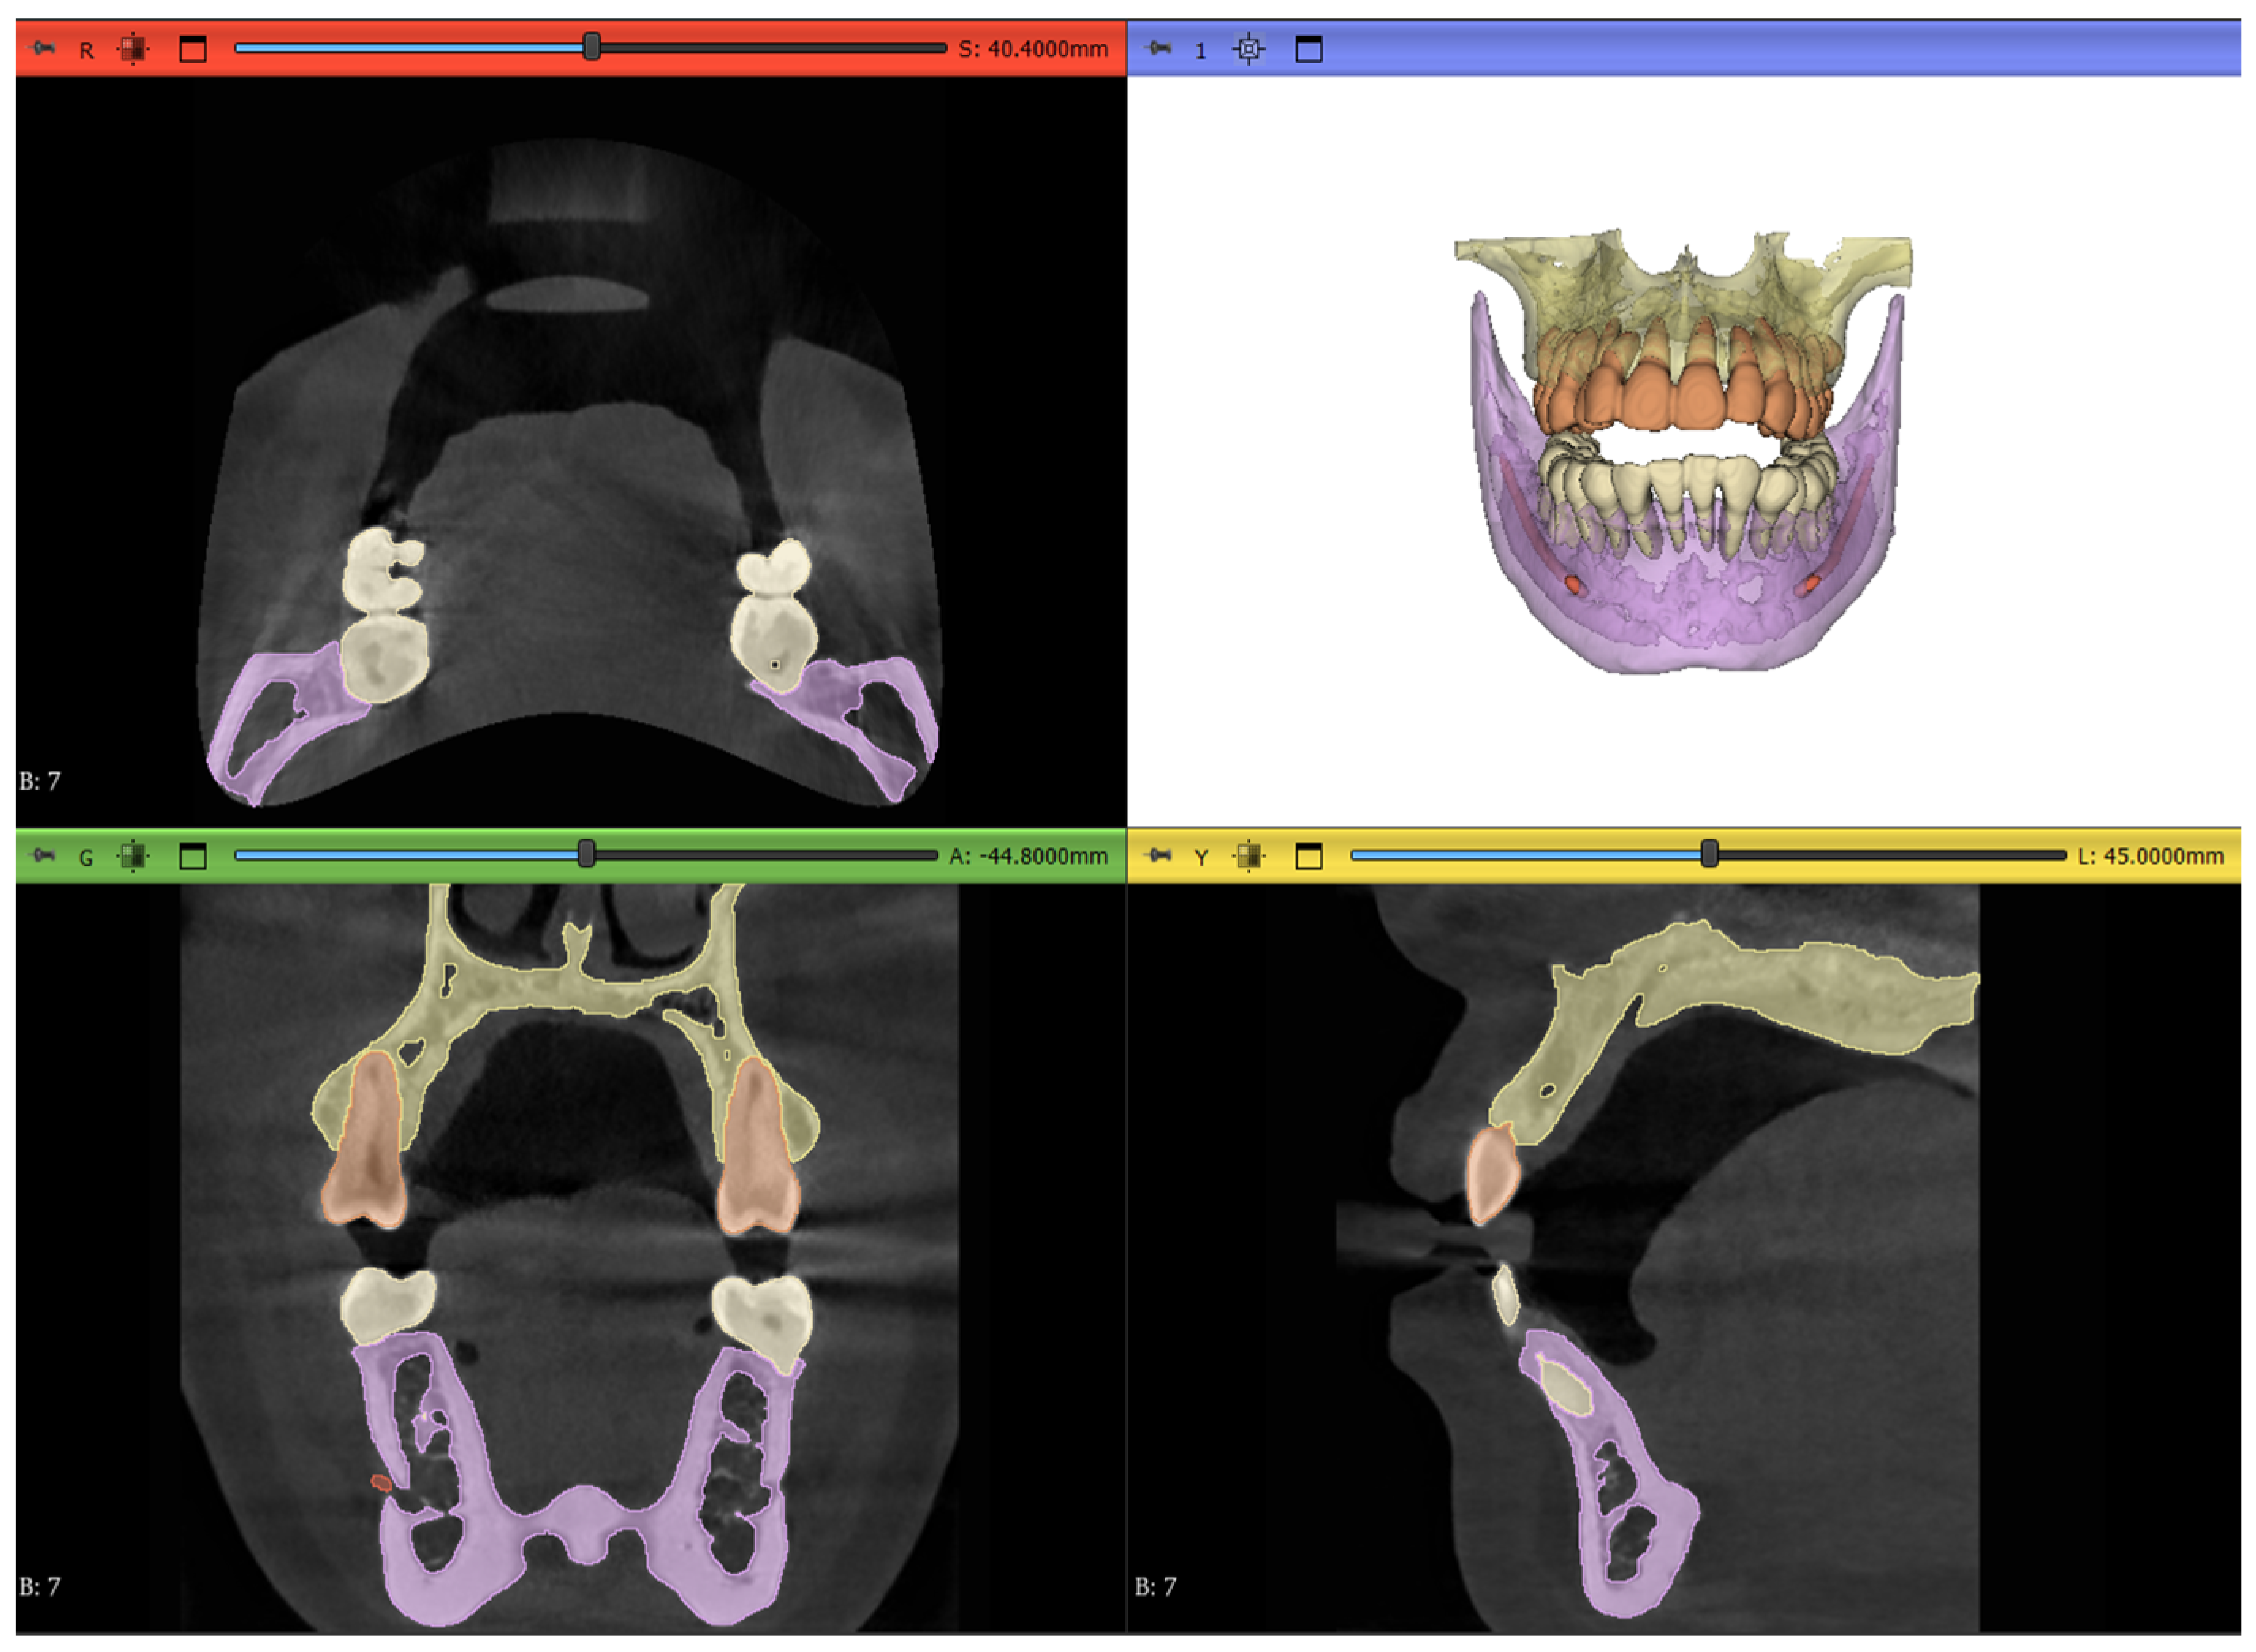

2.7. Workflow 4: Automated DentalSegmentator

Developed by Dot et al. [25], this extension automatically segments maxillofacial CT or CBCT scans into the following 5 different segmentation layers, as shown in Figure 15:

Figure 15.

The output result of running the segmentation model on Dataset 1 of the study.

- Maxilla and upper skull

- Mandible

- Upper teeth

- Lower teeth

- Mandibular canal

This extension offers an extremely simple interface with just one parameter to tweak in regard to surface smoothness; for our specific datasets, this parameter was kept at the default value of 0.5. There is also an option to run the model on the CPU if the computer does not have a cuda-compatible GPU; however, this will understandably take more time to complete.

An acknowledged limitation of the extension by the authors is its inability to offer individual tooth labeling. Thus, a manual step was performed to isolate the tooth of interest by removing the connecting pixels to the adjacent teeth and then keeping the island of pixels belonging to the tooth while discarding all other islands. This is shown in Figure 16.

Figure 16.

The results of segmentation using the automated model: (a) initial connection between adjacent teeth immediately after running the model, (b) erasing pixels of connection, and (c) isolated tooth of interest.

Although some imperfections still persisted in the outputs of the segments, such as mislabeling of the orthodontic brackets and wires as part of the tooth or failing to recognize the root canals, as shown in Figure 17a and Figure 17b, respectively, no manual refinement was carried out to correct these errors. The reason for this decision was to fully test the autonomous nature of the extension and evaluate it against the manual segmentation. In Figure 17, the orange pixels belong to the “upper teeth” layer while the yellow pixels belong to the “Maxilla and upper skull” layer.

Figure 17.

Limitations of the automated extension: (a) braces are considered part of the teeth and (b) root canals are not recognized, as shown by the red arrow.